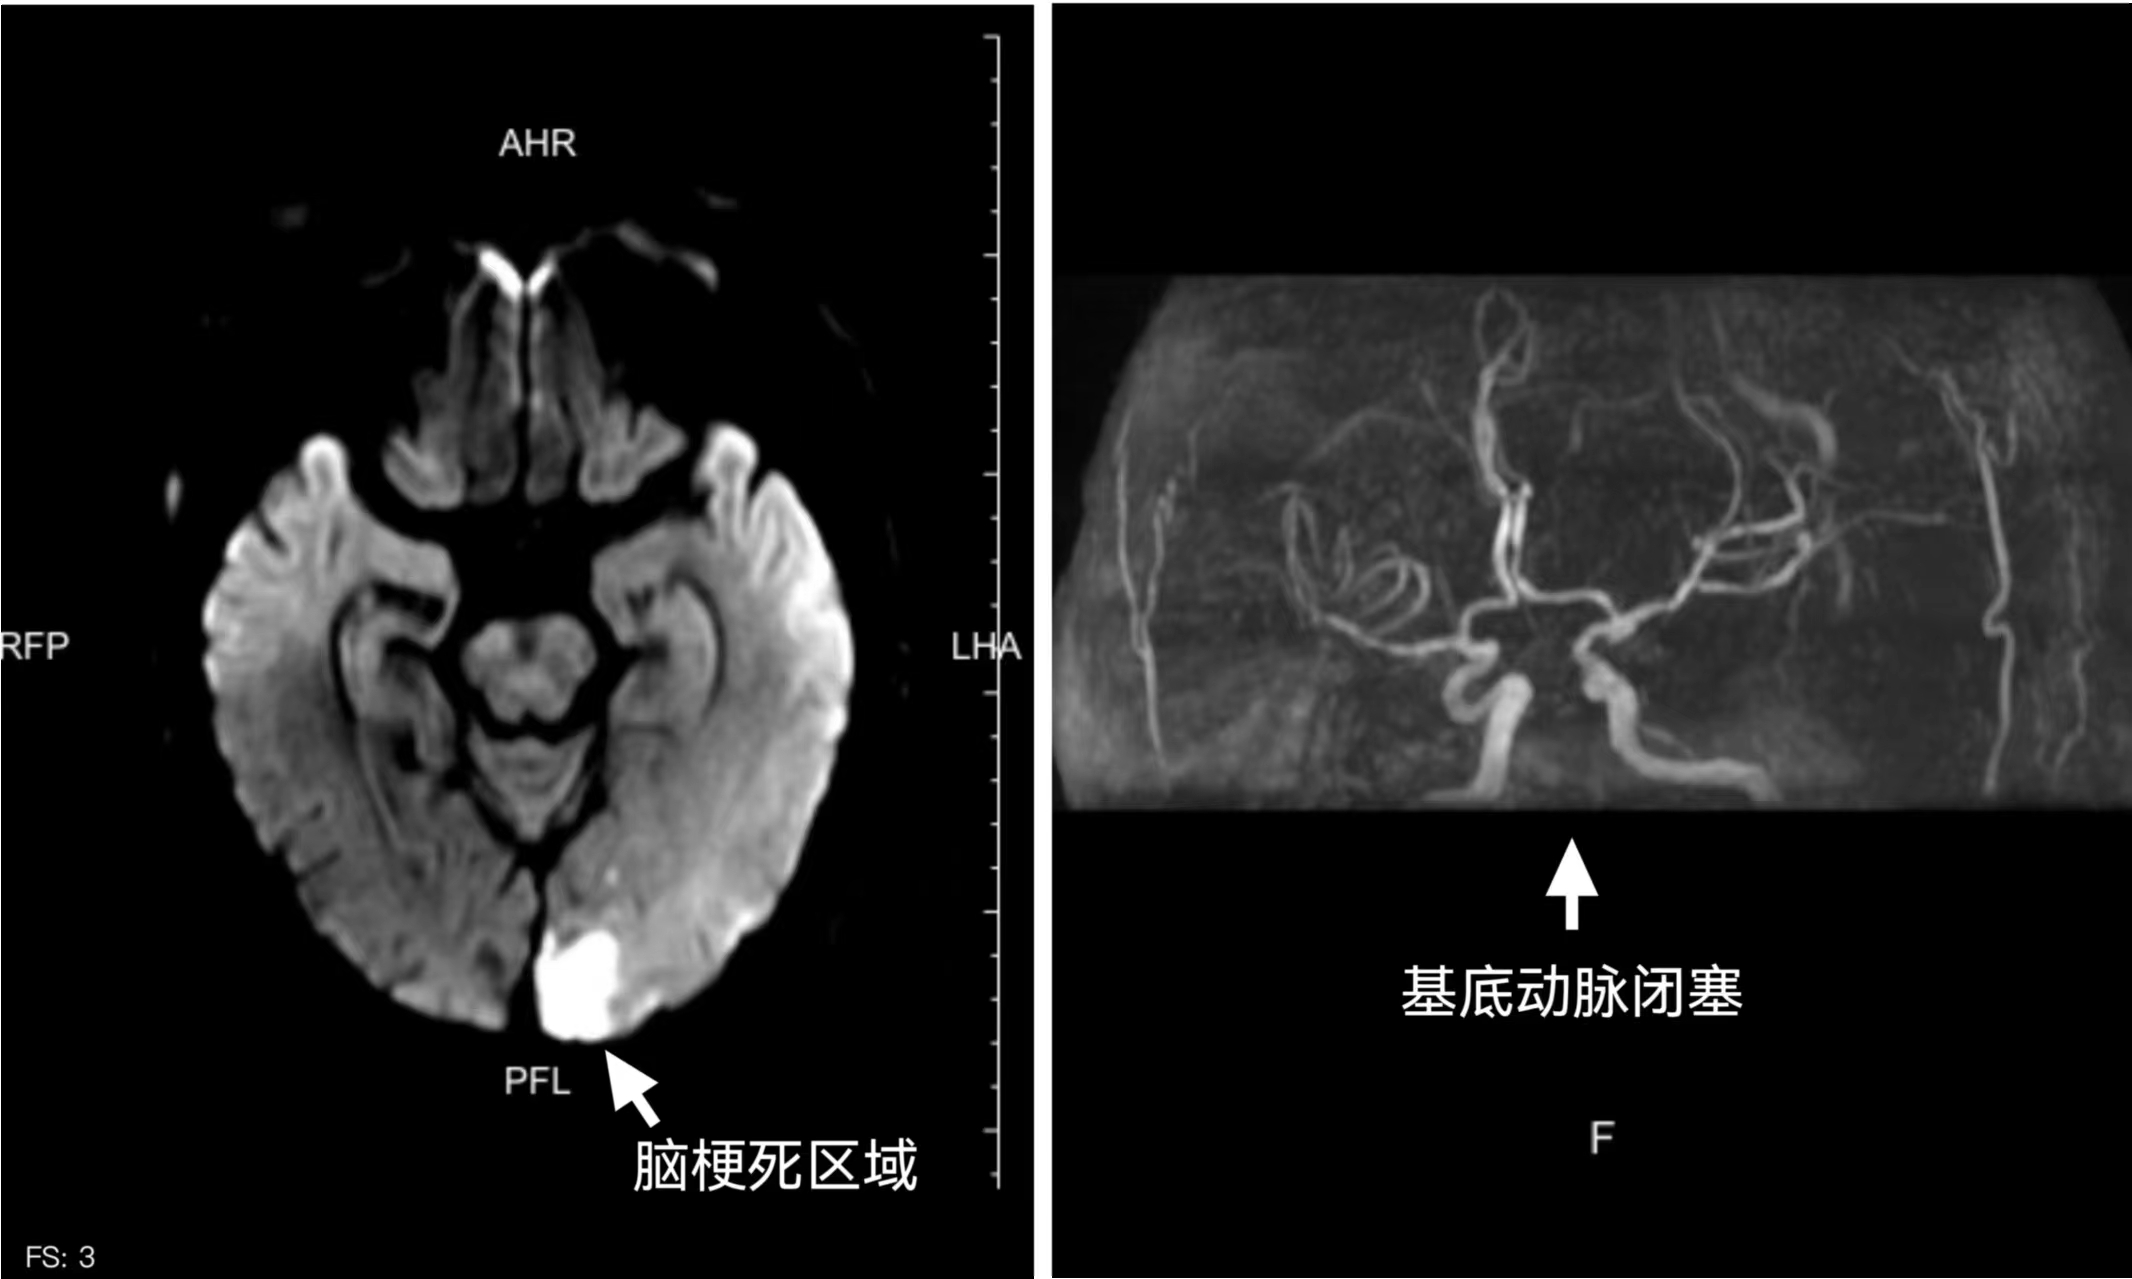

北院神经内科王丽羽医生已接到院前电话通报,早已在急诊科等候。经过快速评估,迅速判断为急性脑卒中后,立即启动卒中绿色通道,通过快速完善头部CT排除脑出血,确定为急性脑梗死。因为王大爷不能确切地说明发病时间,于是医生对其进行快速急诊颅脑磁共振检查评估,8分钟后结果提示为后脑区多发急性脑梗死病灶,已超过静脉溶栓时间窗,更为棘手的是,掌管呼吸心跳的“生命中枢”——颅内大血管基底动脉已经闭塞。

颅脑磁共振检查结果显示患者系脑梗死(左)及基底动脉闭塞(右)。